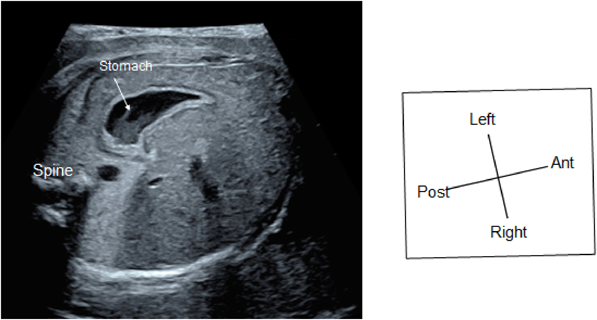

(1) Fetal Laterality: Identifying the Left and the Right Sidedness of the Fetus (Fig. 1)

When the apex of the heart and stomach are not on the left of the fetal body, situs inversus or visceral heterotaxy is indicated, and there is a high probability of complex congenital heart diseases. The fetus should only be examined after the left and the right of the body is identified. No standard method has been established for identifying the dorsal, the ventral, the left, and the right sides. One method typically applied is:

(2) Abdominal Cross-Section

The horizontal section should be continued down to the abdomen to confirm the location of the stomach. When the stomach is on the right or when the location of the stomach is inconsistent with the heart, congenital heart disease is strongly suspected (Fig. 2).